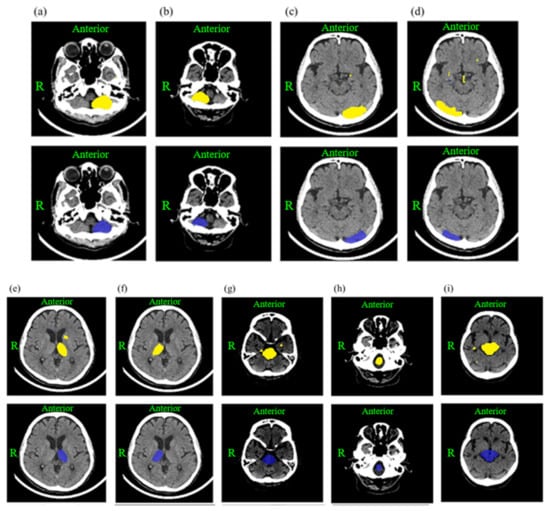

2.3. Deep Learning Model Development and Training

2.4. Calculation of the Prediction Score